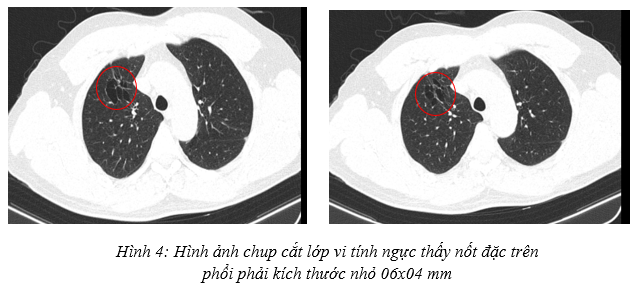

Cắt lớp vi tính ngực: Nhu mô thùy trên phổi phải có nốt đặc bờ không đều kích thước 6x4mm, xung quanh có các ổ giãn phế nang và các dải xơ co kéo nhẹ nhu mô phổi, hạn chế đánh giá tính chất ngấm thuốc do kích thước nhỏ. Ngoài ra nhu mô thùy trên có vài nốt đặc nhỏ <4mm, giới hạn rõ, bờ đều. Không thấy giãn phế quản – phế nang.

Siêu âm hạch vùng cổ: Không phát hiện hạch bất thường.

Chụp cắt lớp vi tính ổ bụng: Chưa phát hiện tổn thương thứ phát.

Nhận xét: Như vậy theo tiêu chuẩn đánh giá đáp ứng khối u RECIST 1.1, bệnh đáp ứng một phần. Trên các phương tiện đánh giá hình ảnh như chụp cắt lớp vi tính ngực, bụng, cộng hưởng từ sọ não không thấy tổn thương bất thường nghi ngờ thứ phát. Về mặt lâm sàng, bệnh nhân hoàn toàn ổn định, không sờ thấy hạch cổ, hạch thượng đòn, xét nghiệm chỉ điểm u giảm về mức bình thường, ngoài ra bệnh nhân không gặp tác dụng phụ của phác đồ điều trị -> Xử trí: Bệnh nhân chuyển sang phác đồ duy trì Atezolizumab – Bevacizumab mỗi 3 tuần/lần cho đến khi bệnh tiến triển hoặc không dung nạp điều trị.